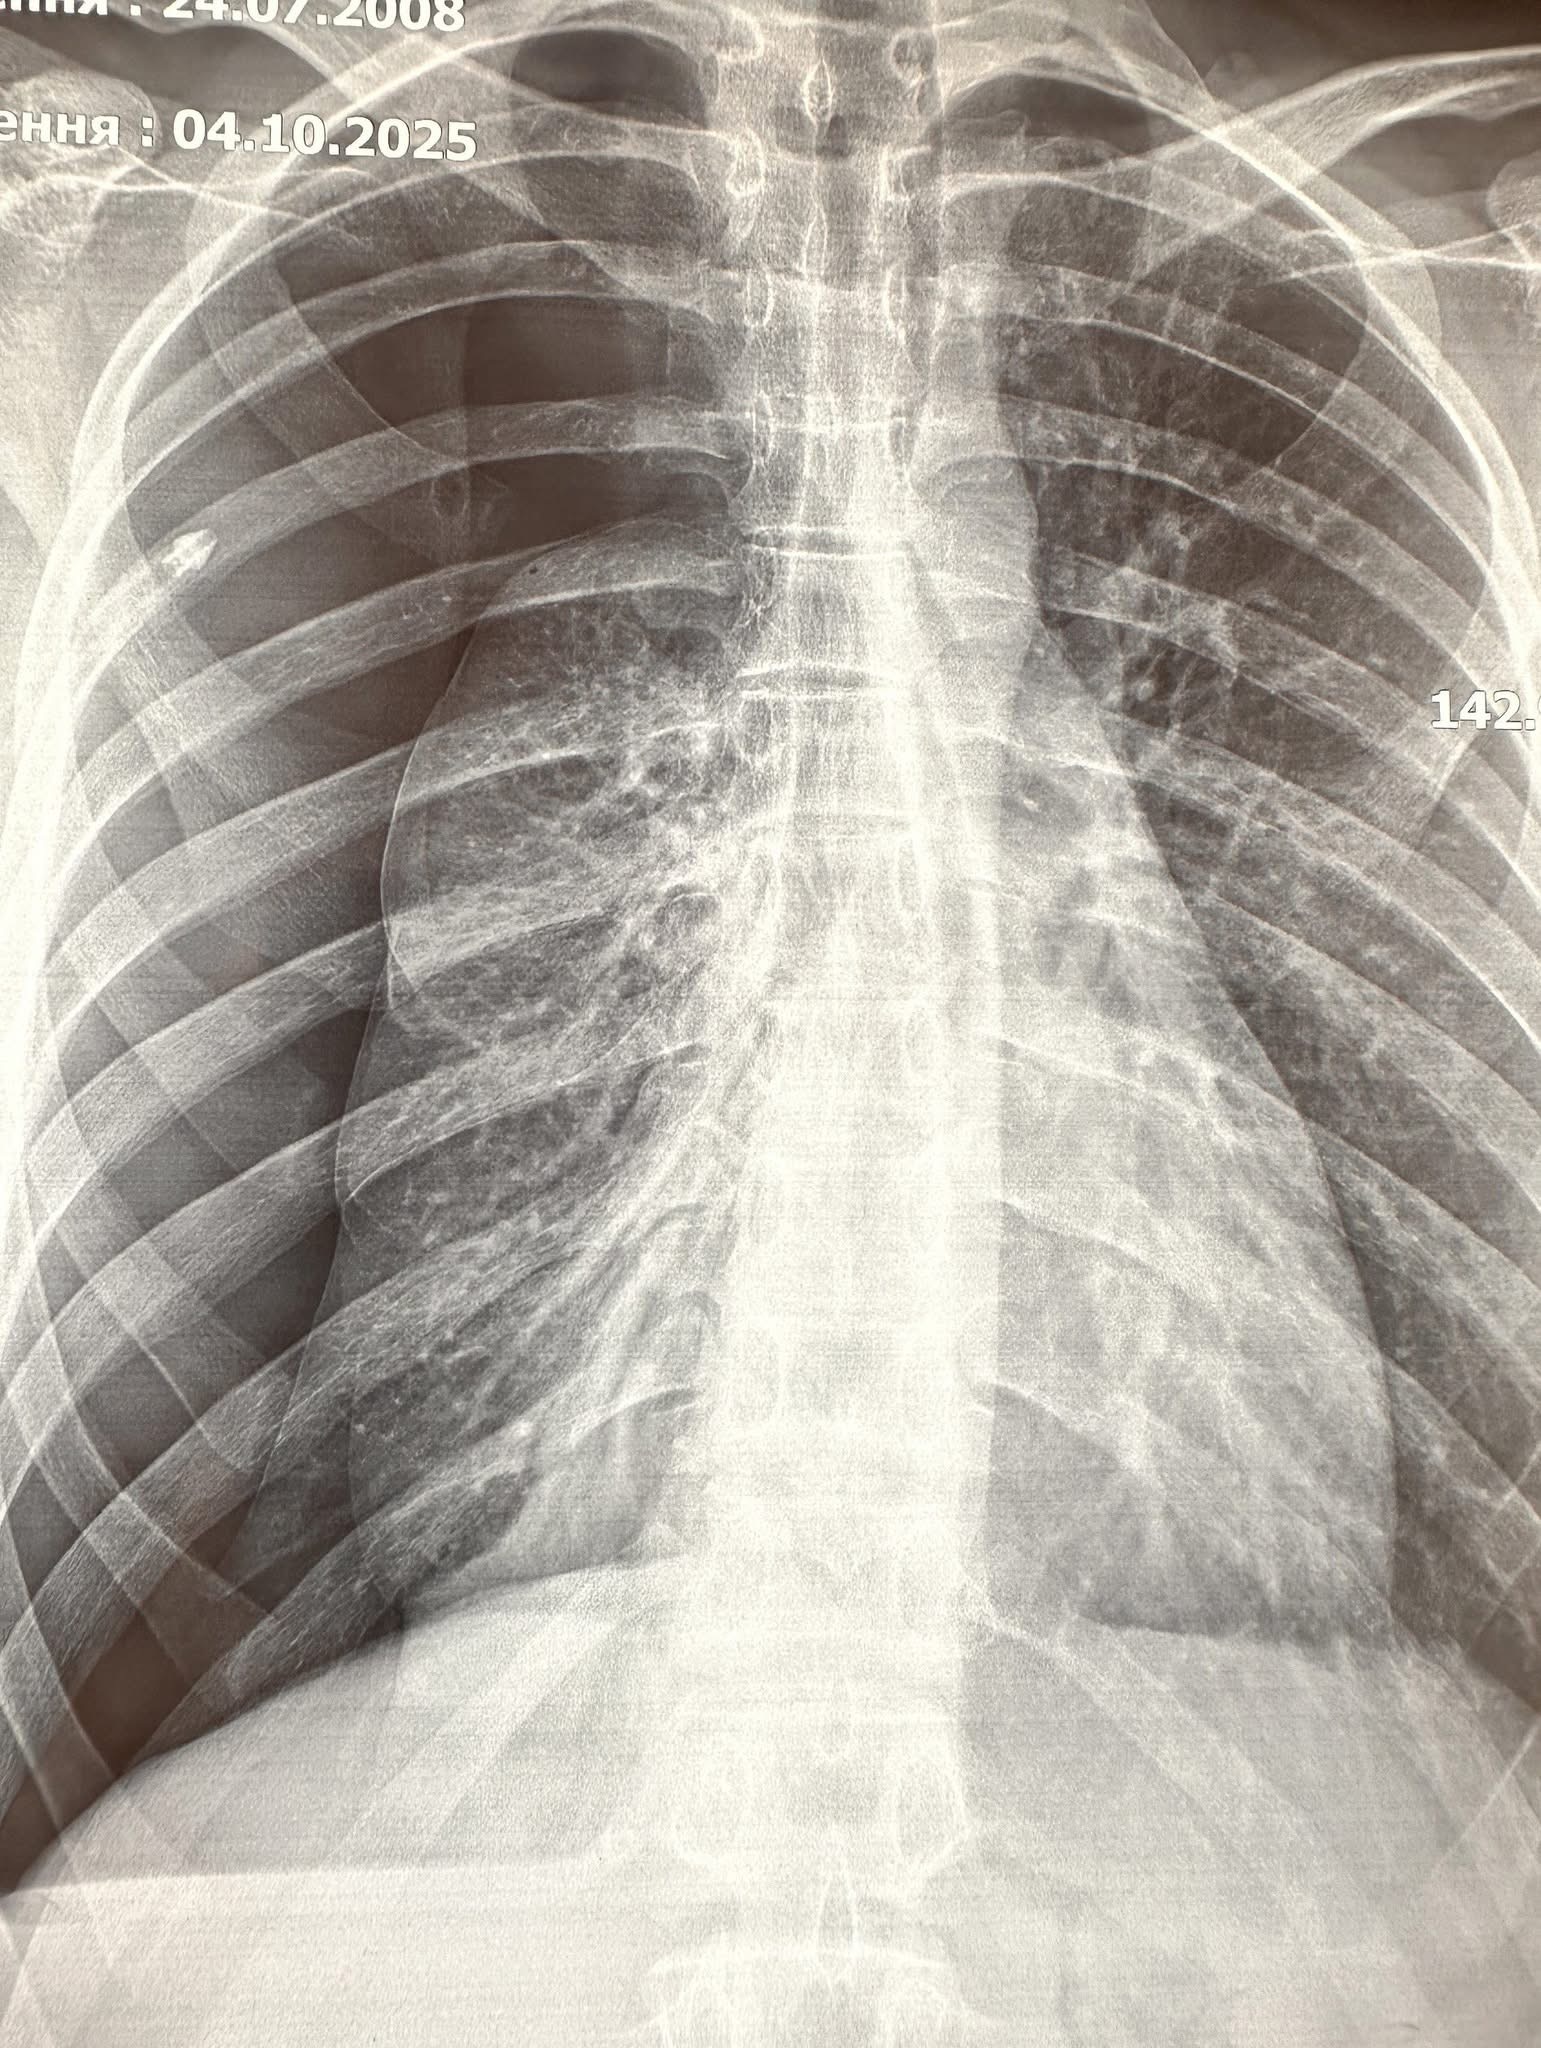

При обстеженні встановлено попередній діагноз – спонтанний пневмоторакс справа.

Проведено дренування плевральної порожнини, але в динаміці ефекту в лікуванні не було. При дообстеженні встановлено діагноз – бульозна хвороба правої легені, правобічний пневмоторакс.